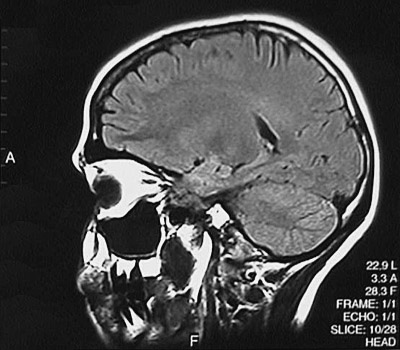

This is a normal sagittal FLAIR MRI scan demonstrating the view to the left of midline at the orbit with the frontal lobe and parietal lobe and occipital lobe and cerebellar hemisphere and orbit and thalamus and hippocampus.